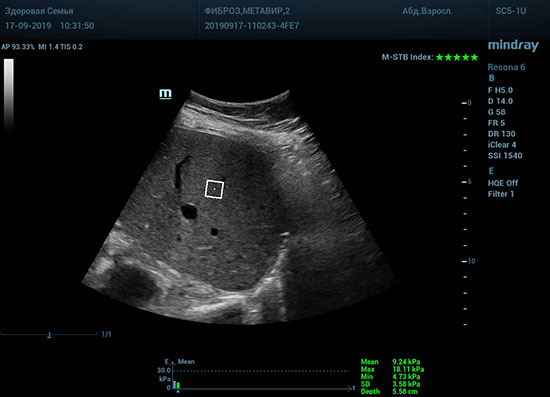

Определение плотности печени. Не ошибся ли оператор при измерении эластических свойств печени? Для оценки критериев качества предусмотрен индекс MBT, который покажет насколько «твердой» была рука оператора и двигалась ли печень. При MBT 5* рука тверда и показатели достоверны. Для оценки качества результатов используется IQR индекс, отображающий колебания показателей в точке измерения при расчете медианы. Показатели при IQR <30% считаются приемлемыми. Техника сканирования через межреберные промежутки требует размещение окна интереса на несколько сантиметром ниже капсулы, для исключения эффекта реверберации. Установка ROI на паренхиму без захвата сосудов, для исключения погрешностей измерения.

Стадия фиброза определяется по системе METAVIR Staging, построенной на данных биопсии и сопоставлении с данными эластографии. Своевременная диагностика фиброза, и начало его лечения, залог благоприятного исхода заболевания.